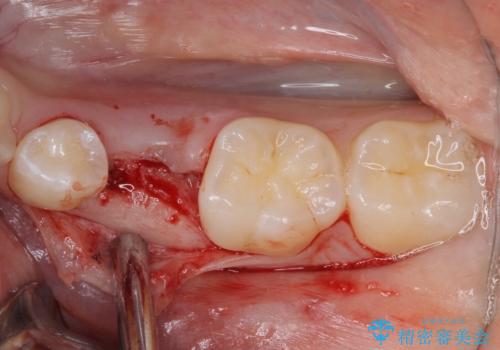

左下には後続永久歯の欠損した乳歯が残存しており、叢生を相まって咬合関係が乱れていました。

乳歯は抜歯し、インビザラインにて矯正治療を行いながら、並行してインプラントによる補綴治療を行うこととしました。

矯正治療が終わるタイミングに合わせてインプラントの埋入を行っていたので、矯正治療を終了すると同時にセラミック補綴治療を行えました。